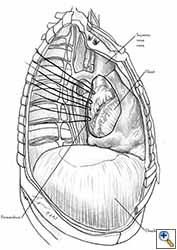

Medium and large-sized (Figures 1a, 1b) defects generally result after pneumonectomy for advanced central lung tumours which invade the pericardium (T3 invading pericardium), thus requiring reconstruction (Figure 1c). To achieve a curative resection, negative pericardial resection margins must be obtained and checked microscopically. More invasive tumours (T4 invading cardiac structures) require partial atrial resection and pericardiectomy associated with pneumonectomy.

| Figure 1c: Intraoperative aspect of pericardioplasty with Marlex mesh after right completion pneumonectomy with partial pericardiectomy. |

Video 1 depicts a pericardial reconstruction with Marlex after a right completion pneumonectomy with pericardiectomy for lung adenocarcinoma (see also Figure 1). The technique of pericardial reconstruction after the resection of invasive mediastinal tumours is illustrated in Figures 8a-c). Video 2 depicts a pericardial reconstruction with Mersilene mesh after the resection of a malignant thymoma invading the anterior pericardium (see also Figure 4b). The technique of right pericardial reconstruction after extrapleural pneumonectomy is illustrated in Figures 9a and 9b). Video 3 depicts a pericardial reconstruction using Gore-Tex Dual Mesh after a left extrapleural pneumonectomy (see also Figure 3). Care must be taken to prevent constriction (Figure 10).